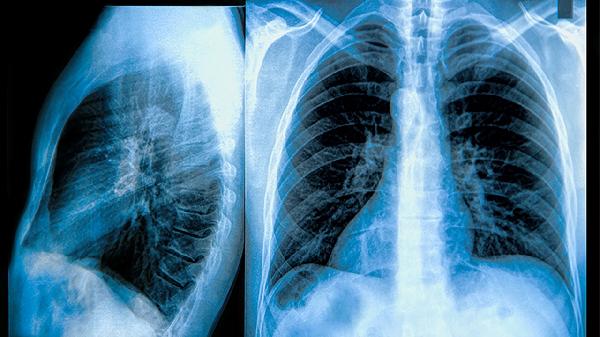

慢阻肺是一種以持續(xù)氣流受限為特征的慢性氣道炎癥性疾病,主要癥狀包括慢性咳嗽、咳痰、活動后氣短或呼吸困難。

慢性咳嗽是慢阻肺最早出現(xiàn)的癥狀,初期可能表現(xiàn)為間歇性咳嗽,早晨較為明顯,隨著病情進(jìn)展可發(fā)展為整日咳嗽。這種咳嗽通常與氣道黏膜長期受到煙霧、粉塵等有害氣體刺激,導(dǎo)致黏液分泌增多和氣道高反應(yīng)性有關(guān)。咳嗽本身是氣道的一種防御性反射,旨在清除過多的分泌物和吸入的顆粒物。對于慢阻肺患者,單純鎮(zhèn)咳并非主要治療目標(biāo),治療重點在于控制氣道炎癥和舒張支氣管?;颊邞?yīng)避免吸煙及接觸二手煙、廚房油煙等刺激性氣體,在醫(yī)生指導(dǎo)下使用支氣管舒張劑如沙丁胺醇?xì)忪F劑、異丙托溴銨氣霧劑,或聯(lián)合吸入糖皮質(zhì)激素如布地奈德福莫特羅粉吸入劑,以減輕氣道炎癥、緩解咳嗽癥狀。

咳痰是慢阻肺的常見癥狀,患者通常會咳出少量白色黏液痰或漿液性泡沫痰,急性加重期痰量可能增多,或轉(zhuǎn)為膿性痰。痰液的產(chǎn)生源于氣道杯狀細(xì)胞增生和黏液腺肥大,導(dǎo)致黏液分泌過度。痰液潴留不僅加重氣道阻塞,還可能繼發(fā)細(xì)菌感染。因此,促進(jìn)痰液排出是管理的重要環(huán)節(jié)。患者應(yīng)保證每日充足飲水,有助于稀釋痰液。在醫(yī)生指導(dǎo)下,可使用祛痰藥物如鹽酸氨溴索口服溶液、乙酰半胱氨酸泡騰片或標(biāo)準(zhǔn)桃金娘油腸溶膠囊,幫助降低痰液黏稠度,使其易于咳出。對于痰液黏稠難以咳出的患者,家屬可協(xié)助其進(jìn)行拍背排痰。

活動后氣短或呼吸困難是慢阻肺的標(biāo)志性癥狀,早期僅在勞力時出現(xiàn),之后逐漸加重,以致在日?;顒由踔列菹r也感到氣促。這主要是由于氣道壁增厚、管腔狹窄、彈性回縮力下降以及肺泡結(jié)構(gòu)破壞導(dǎo)致氣體交換面積減少所致。呼吸困難會嚴(yán)重影響患者的活動能力和生活質(zhì)量。管理此癥狀的核心是長期堅持規(guī)范治療以延緩肺功能下降。患者需遵醫(yī)囑規(guī)律使用長效支氣管舒張劑,如噻托溴銨粉吸入劑、茚達(dá)特羅格隆溴銨吸入粉霧劑,必要時聯(lián)合吸入糖皮質(zhì)激素。此外,在專業(yè)指導(dǎo)下進(jìn)行肺康復(fù)訓(xùn)練,如縮唇呼吸、腹式呼吸及循序漸進(jìn)的耐力鍛煉,有助于改善呼吸肌功能,提高運(yùn)動耐力。

部分慢阻肺患者,特別是在急性加重期或合并氣道高反應(yīng)性時,會出現(xiàn)喘息和胸悶感。喘息是由于氣流通過嚴(yán)重狹窄的氣道時產(chǎn)生的高調(diào)呼吸音。胸悶則是一種主觀的胸部壓迫感或呼吸不暢感。這些癥狀的出現(xiàn)往往提示氣道痙攣或炎癥加重。當(dāng)出現(xiàn)喘息或胸悶加重時,患者應(yīng)首先使用醫(yī)生處方的短效支氣管舒張劑如硫酸特布他林霧化吸入用溶液進(jìn)行緊急緩解,并密切觀察癥狀變化。如果癥狀持續(xù)不緩解或進(jìn)行性加重,可能預(yù)示著急性加重,需要及時就醫(yī)。醫(yī)生可能會調(diào)整治療方案,例如短期加用口服糖皮質(zhì)激素如潑尼松片,或進(jìn)行抗感染治療。

隨著慢阻肺病情進(jìn)展到中重度階段,患者可能出現(xiàn)疲勞、食欲減退、體重下降、肌肉萎縮等全身性癥狀。這些癥狀與長期慢性缺氧、系統(tǒng)性炎癥反應(yīng)消耗增加、以及呼吸困難導(dǎo)致進(jìn)食和活動減少有關(guān)。全身性癥狀的出現(xiàn)是疾病嚴(yán)重程度增加和預(yù)后不良的信號。針對性的管理包括在醫(yī)生指導(dǎo)下進(jìn)行長期家庭氧療,糾正低氧血癥,改善組織供氧。同時,應(yīng)保證均衡的營養(yǎng)攝入,適當(dāng)增加優(yōu)質(zhì)蛋白如魚肉、雞蛋、牛奶的攝入,必要時可咨詢臨床營養(yǎng)師。對于存在明顯肌肉消耗和乏力的患者,在病情穩(wěn)定期,應(yīng)在康復(fù)治療師指導(dǎo)下進(jìn)行個體化的力量訓(xùn)練,以改善肌肉功能和體能狀態(tài)。